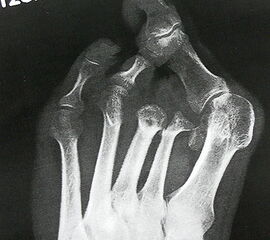

Wegen des Risikos einer Ulzeration am Metatarsalekopf (Abb. 14) sollte die Exartikulation im Grundgelenk vermieden werden. Günstiger ist es, falls möglich, einen kurzen Grundglied­stumpf als Platzhalter zu belassen (Abb. 15). Wenn Zehen in eine Lücke zu kippen drohen, kann die mit einem Platzhalter verhindert werden (Abb. 16, 17)

Es ist ungünstig, wenn wenige Kleinzehen lateral belassen werden. Das führt zum Kippen der Nachbarzehen oder zur Fehlstellung der verbliebenen Zehen (Abb. 18 - 20) und schließt eine optimale schuhtechnische Versorgung aus. Weitere Druckulzera sind zu erwarten. Die Großzehe kann als einzige Zehe belassen werden, wobei dann bisweilen die Arthrodese im Großzehengrundgelenk zur Stabilisierung ratsam ist (Abb. 21, 22).